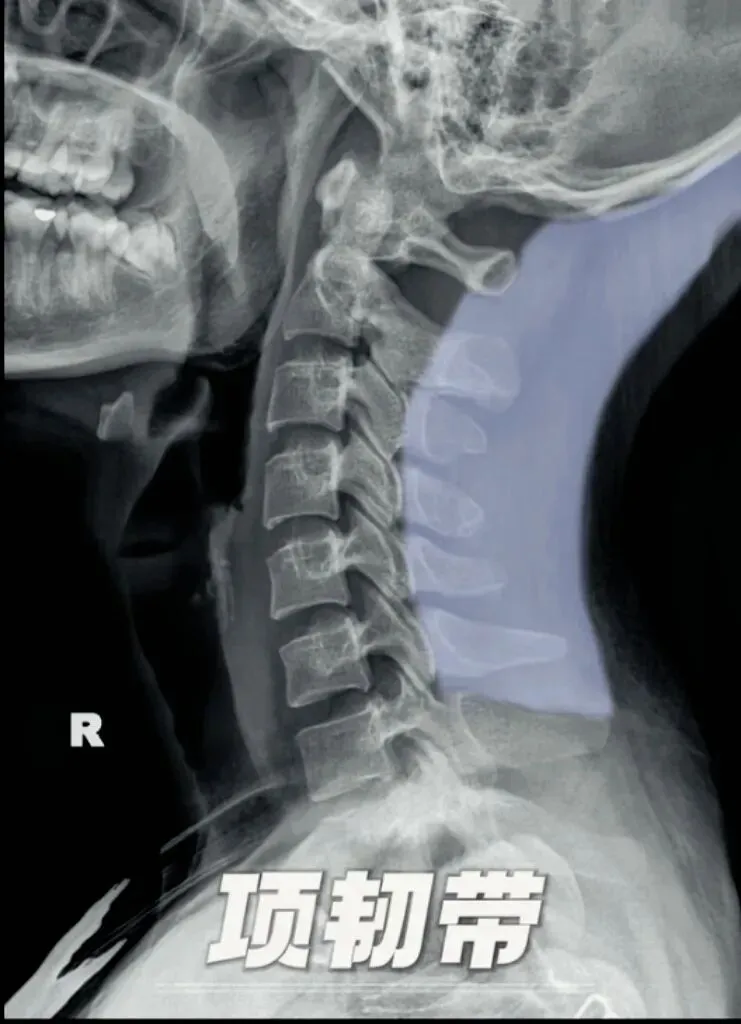

四,韧带钙化。颈椎的韧带有很多条,虽然X线无法直接显示颈椎韧带,但是我们可以通过解剖结构中韧带的走形区来间接判断。韧带钙化的原因诸多,主要从颈椎侧位片上进行观察。我们来学习几个常见的颈椎韧带钙化。首先是项韧带,位于枕外隆凸,枕外嵴、寰椎后结节及第二至第七颈椎棘突之间,

主要功能是限制颈部过度前屈,维持颈部姿势稳定,也是最常见的颈椎韧带钙化之一,多发生于颈4至6椎体的后方。